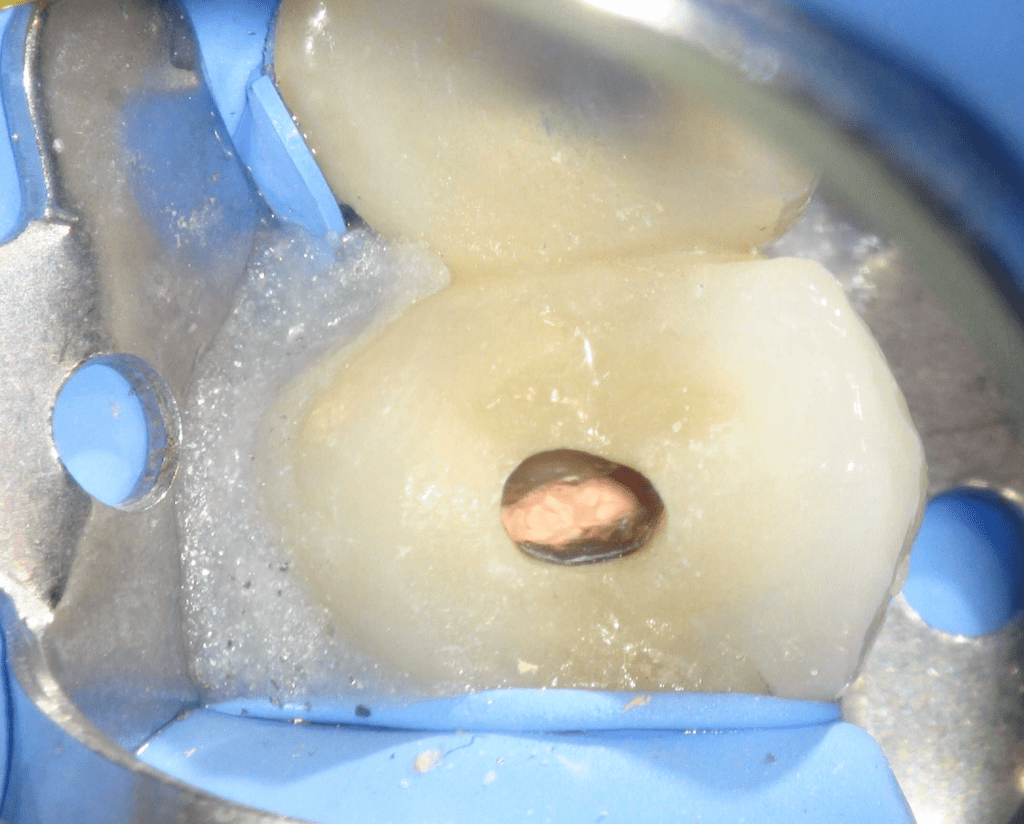

Fisura, remoción amalgama para explorar